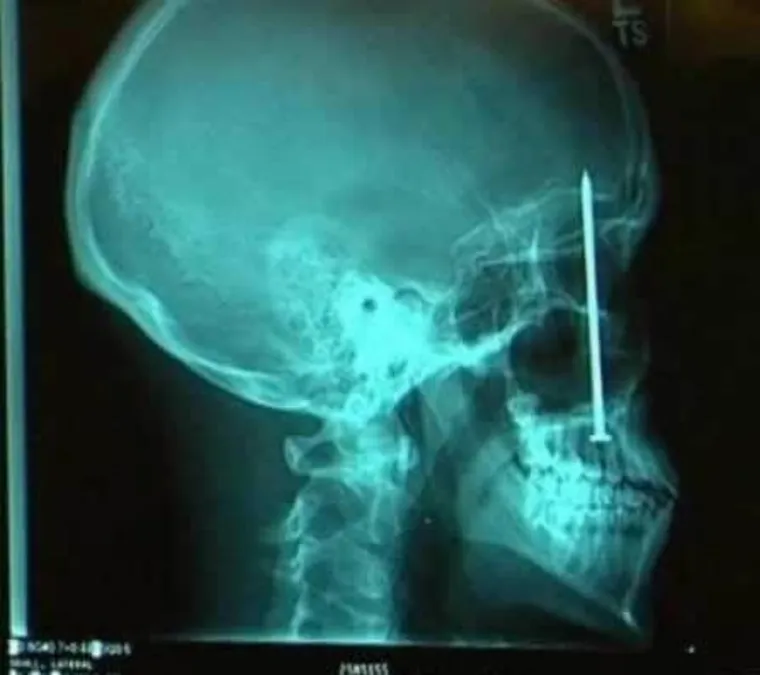

BOLJET ĆE VAS OD SAMOG POGLEDA... Rengenske snimke od kojih će vas proći trnci

Došao je zubaru žaleći se na zubobolju